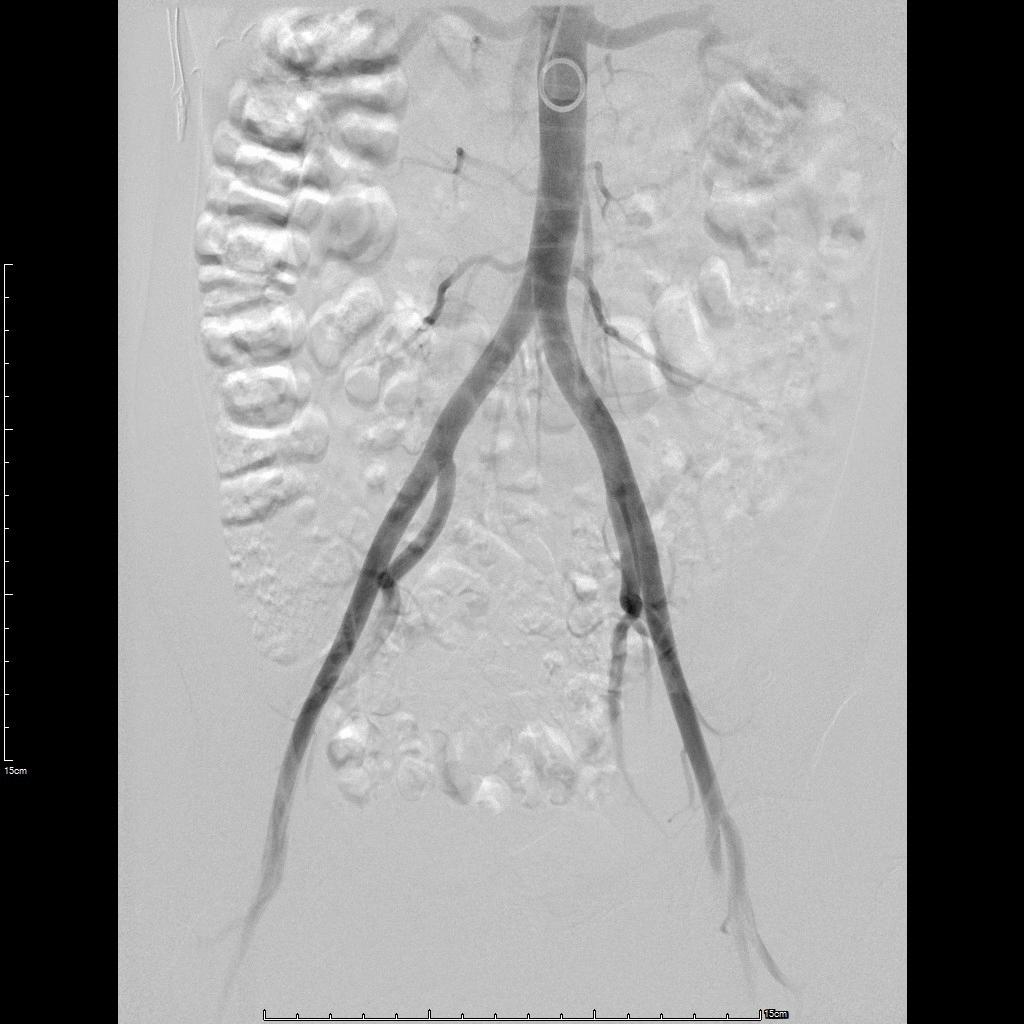

- 经左侧桡动脉穿刺置管,行腹主动脉造影显示双侧子宫动脉增粗、迂曲。